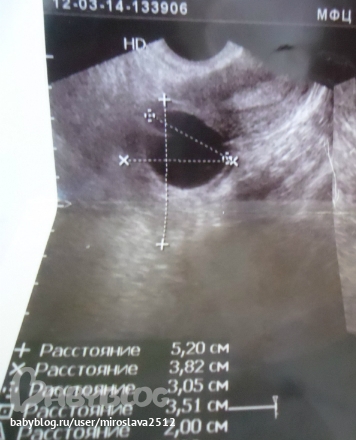

Вообщем надумала сходить на узи чисто от любопытства...и что меня там ожидалооо....Мой Дф 1.85см вырос до 3.14см ((((неужели киста? ?!!!

Или это киста желтого тела?! Фото снизу скину...может кто понимает и скажет мне что это....

Вот например подтвержденное ЖТ и тоже около 30 мм.

Ну и где тут что неровное? И где вкрапления?А вот вам киста (под вопросом):

Отличить сложно. Но если есть жидкость,а у вас есть, тогда это ЖТ.

Больше похоже на фолликулярную кисту! Но есть овуляторный бугорок - может и лопнет еще...

Ооочень сложно понять... Толи это место разрыва уже, толи нет... Но по кровотоку ощущение что это формирование ЖТ!

Да она есть,именно я правой стороны гле и Дф был... значит думаете что фоллик лопнул, и желтое тело переросло в кисту Жт!? Эндометрий еще 1.22см

Да, думаю фолик лопнул — все таки и сам не маленький был, и 10 тыс ХГЧ... Да и жидкость сомнений не оставляет! А по размерам это киста Жт — у меня в Б цикл кстати тоже была киста ЖТ)

Не хочу Вас расстраивать, но на мой взгляд, это все же больше похоже на фолликулярную кисту. У кисты желтого тела не такая однородная внутренняя консистенция. Я так понимаю, возможности сдать кровь на прогестерон у Вас нет, раз улетаете завтра? Если найдете такую возможность-сдайте утром в той лаборатории,где Вам могут выслать результат по смс или по почте. Прогестерон мог бы прояснить картину- если его уровень будет достаточным для лютеиновой фазы,значит это все-таки киста желтого тела (дай Бог чтобы так было), а если прогестерон низкий,как в фолликулярную фазу,то речи о ЖТ быть не может,и кисту придется полечить-помочь ей рассосаться.

я не врач, но по мне похоже очень нафолликулярную кисту (у жт контуры другие, неровные),у самой такая была, изучала вопрос. ей теперь лучше не дать лопнуть.мне тогда таблетки противовоспалительные назначали, м М она ушла.